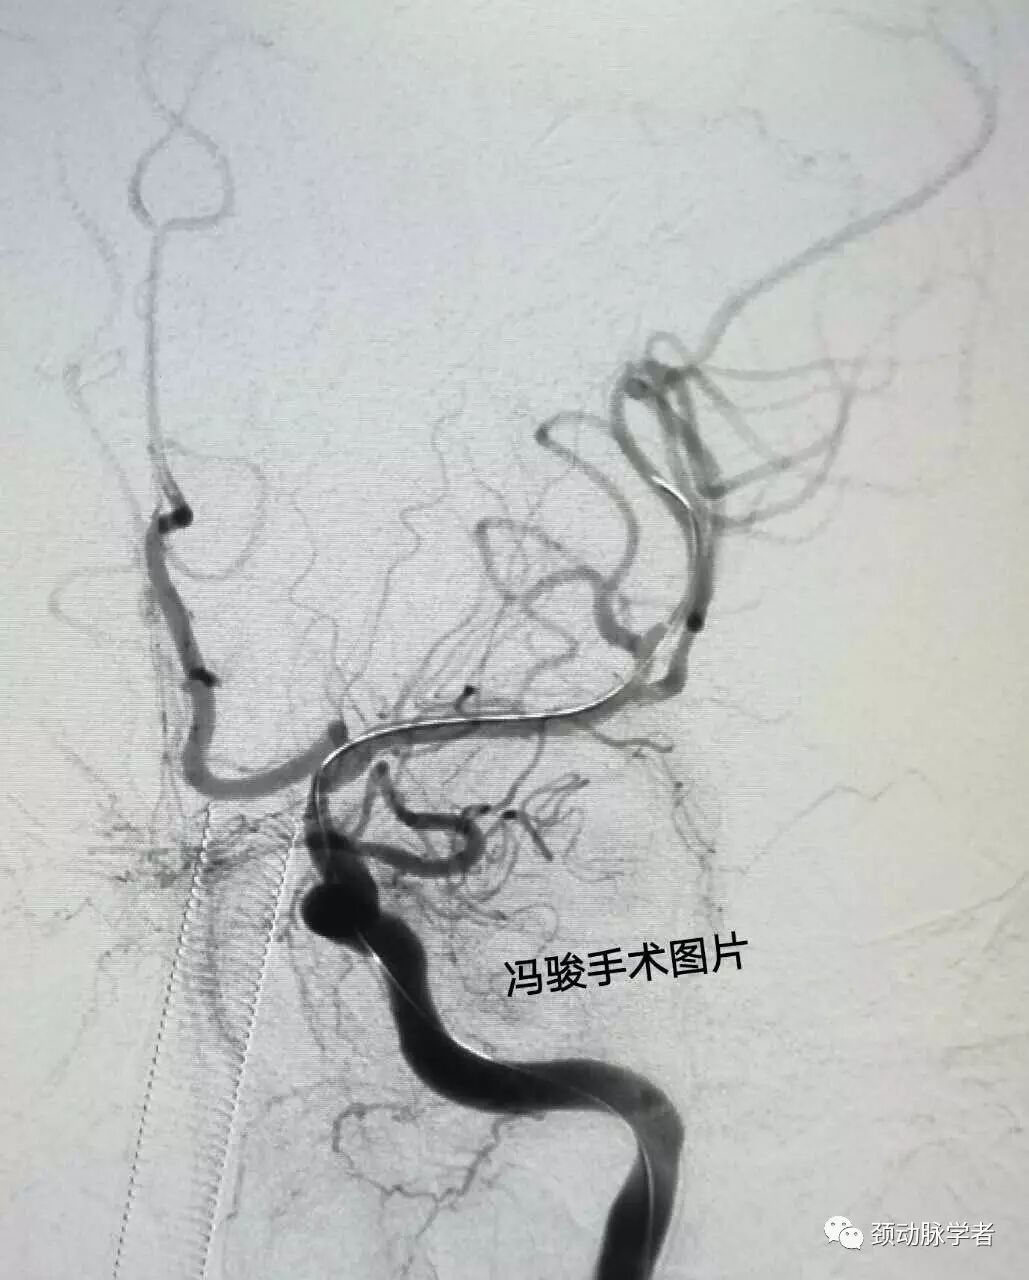

造影显示,右侧颈内动脉完全闭塞,左侧颈内动脉床突上段(颅内段)99%狭窄,后循环向前循环代偿亦不足,患者“命悬一线”!

全麻下,guiding置入左颈内动脉海绵窦,造影显示,床突上段的确99%线样狭窄。

精准定位后,释放2.5-8mm,apollo支架,再次造影显示,狭窄解除,血流通畅。